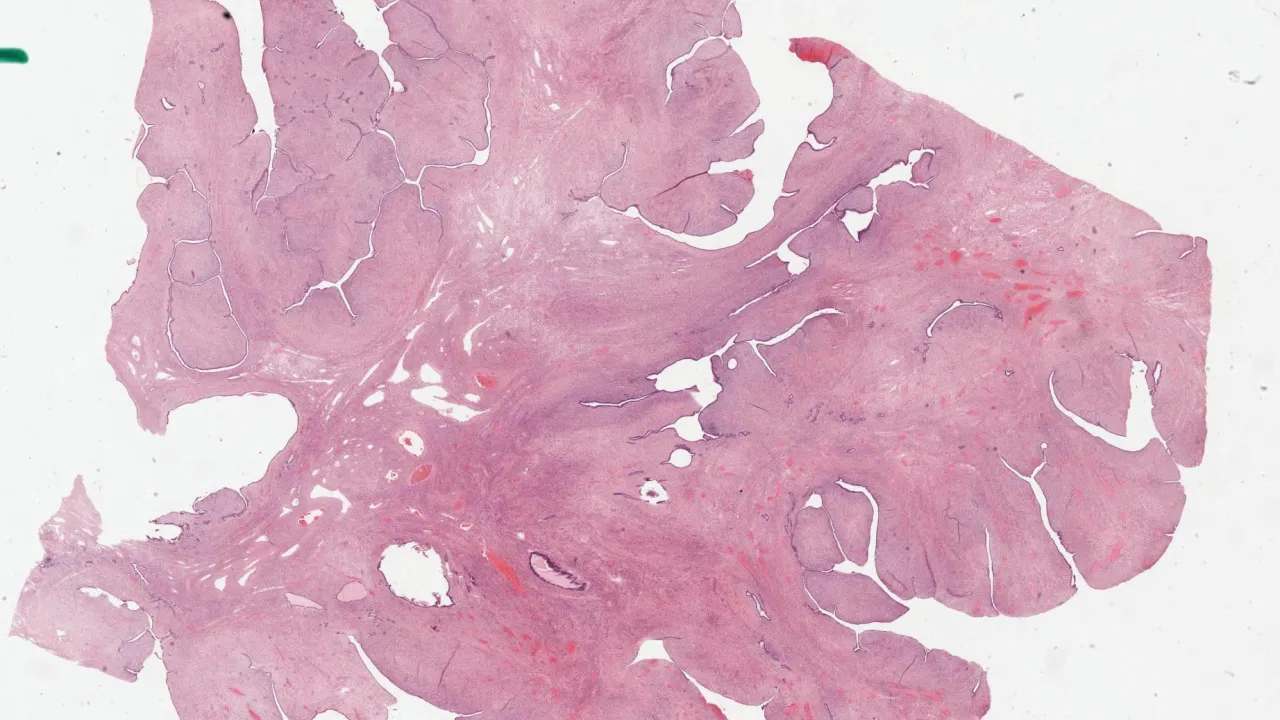

Placenta, Complete hydatidiform mole